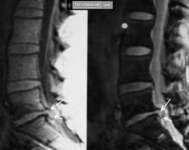

Tanı YöntemleriAtipik hemanjiomun tanısı genellikle görüntüleme yöntemleriyle konur. Bu yöntemler arasında:

Bu görüntüleme yöntemleri, hemanjiomun boyutunu, konumunu ve yapısını belirlemek için kullanılır. Ayrıca, doktorlar histolojik inceleme için biyopsi de alabilirler. Tedavi SeçenekleriAtipik hemanjiom tedavisi, hastanın genel durumu, tümörün boyutu ve belirtilerin şiddeti gibi faktörlere bağlı olarak değişiklik gösterir. Tedavi seçenekleri arasında:

MRG ve BT gibi görüntüleme yöntemleri tanı ve takipte oldukça güvenilirdir. Cerrahi müdahale genellikle sadece şu durumlarda gündeme gelir: şiddetli ağrı, nörolojik defisit riski, patolojik kırık tehlikesi veya hızlı büyüme. Mevcut tedavi seçenekleri arasında gözlem, embolizasyon, radyofrekans ablasyon ve cerrahi yer alır.